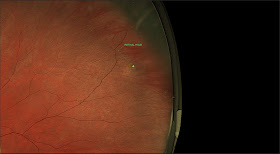

RETINOSCHISIS

Below is a picture of a patient with a retinoschisis with an outer layer break in the retina. The lower arrow points to the break and the higher arrow points to the edge of the schisis. A schisis is a separation of the retina from itself. The edge of the schisis is usually smooth and in a circular pattern as shown here.